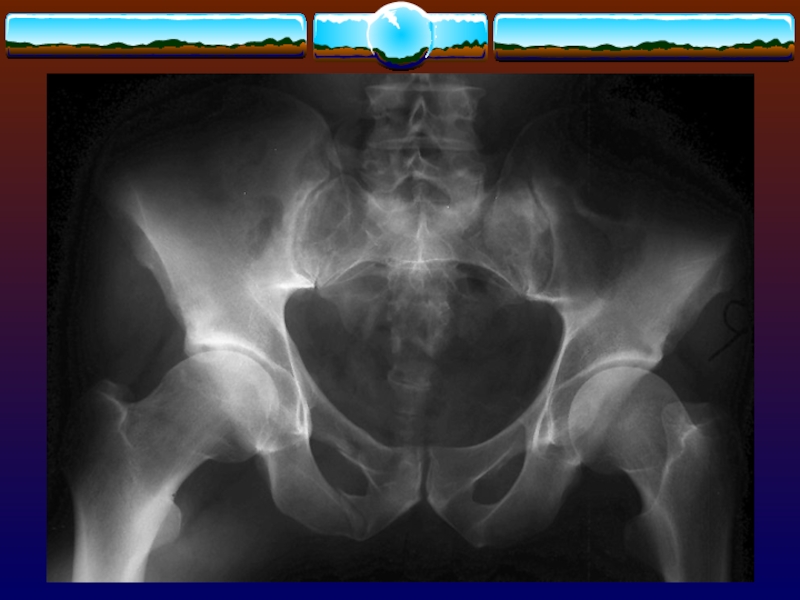

Слайд 67Этиология

ДТП 60 %

падения 30 %

Летальность

общая 15 %

30

% при открытых переломах

45 % у пациентов с гипотензией

при

поступлении

ЭтиологияДТП 60 % падения 30 %Летальность общая 15 % 30 % при открытых переломах 45 % у

Слайд 71Классификация AO/ASIF

Классификация AO/ASIF